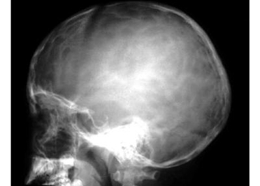

骨質(zhì)疏松:指一定單位體積內(nèi)正常鈣化的骨組織減少,即骨組織的有機(jī)成分和鈣鹽都減少,但骨內(nèi)有機(jī)成分和鈣鹽含量比例仍正常,x 線表現(xiàn)主要為骨密度減低,骨小梁變細(xì)、減少、間隙增寬,骨皮質(zhì)出現(xiàn)分層和變薄現(xiàn)象。疏松的骨骼易發(fā)生骨折。

骨質(zhì)破壞:局部骨質(zhì)為病理組織所代替而造成的骨組織消失,X線表現(xiàn)為骨質(zhì)局限性密度減低,骨小梁稀疏消失而形成骨質(zhì)缺損,其中全無骨質(zhì)結(jié)構(gòu)。

骨質(zhì)增生硬化:是一定單位體積內(nèi)骨量的增多,x線表現(xiàn)為骨質(zhì)密度增高。伴或不伴有骨骼的增大,骨小梁增粗、增多、密集、骨皮質(zhì)增厚、致密。

骨質(zhì)壞死:骨組織局部代謝的停止,壞死的骨質(zhì)稱為死骨。形成死骨的原因主要是血液供應(yīng)的中斷,x線表現(xiàn)是骨質(zhì)局限性密度增高。死骨的形態(tài)因疾病的發(fā)展階段而不同。